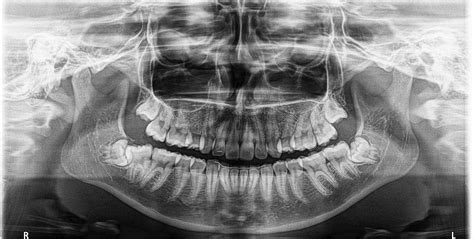

Figura 4 Ortopantomografía pretratamiento.

La ortopantomografía inicial (fig. 4) muestra una dentición mixta, iniciando el segundo período de recambio, con obturaciones a nivel de 16 y 26 y cóndilos mandibulares simétricos.